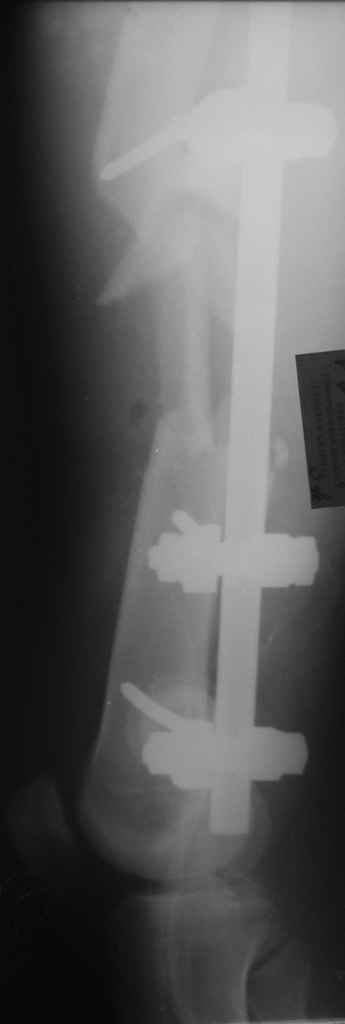

Вчера сделали снимки - положение отломков и осколков вот такое. На перевязке: из раны небольшое кол-во сгустков крови с примесью гноя , хотя бедро спокойное, гипертермии ни локальной ни общей нет. Вопрос: как быть дальше? открывать рану, "чистить" ее, наладить ее перфузию АС, АБ? что делать с осколками, попробовать перекрыть область перелома с фиксацией основных отломков аппаратом. Или осколки убрать и состыковать основные отломки с жутким укорочением и большими проблемами при зашивании раны?

Антон, а где Вы находитесь? Здесь все-таки оптимальнее после санации очага (обработка, лаваж, спейсер с антибиотиками) сделать закрытый

интрамедуллярный остеосинтез либо после спейсера, либо гвоздем с антибактериальным покрытием. Если такой вид помощи недоступен у вас, может быть, есть возможность пациента переправить в другой центр с

большими возможностями?

Свободные костные отломки, несвязанные с живыми мягкими тканями в условиях инфицированного перелома, необходимо удалить.